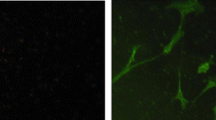

Fluorescence microscopy has been used to track the cell uptake and intracellular distribution of zinc(II) bis(thiosemicarbazonato) complexes that are weakly fluorescent owing to intraligand excitation [20]. The analogous copper(II) compounds are not fluorescent. The new systems with a conjugated pyrene fluorophore are fluorescent even in the presence of paramagnetic d 9 CuII. Cell uptake and the intracellular distribution of CuII L 1 in HeLa cells were determined by confocal fluorescence microscopy, first for a copper(II) bis(thiosemicarbazonato) complex. Differential interference contrast and confocal fluorescence microscopy images of HeLa cells treated with CuII L 1 (50 μM) and fluorescence microscopy images (λex = 405 nm, λex = 410–470 nm) are shown in Fig. 7. These measurements confirmed the cell-uptake data obtained by ICP-MS and showed that CuII L 1 is cell-permeable. There was no apparent cell toxicity at these concentrations as determined by a lactate dehydrogenase assay. The compound localises predominantly in the cytosol, with punctate inclusions, possibly vesicles, also observed within the cytosol. Importantly, considering the potential of pyrene derivatives to bind DNA, we saw no staining of the nucleus with CuII L 1. The lack of fluorescence in the nucleus does not completely preclude the possibility of uptake of the complex in the nucleus. In some cases the fluorophore interacts with DNA in such a way that the emission is quenched or significantly shifted. DNA has been shown to dampen the fluorescence of platinum complexes with an anthraquinone functional group and platinum complexes with a coumarin 120 fluorophore [41, 42]. In the present case, titration of calf thymus DNA into a buffered solution of CuII L 1 resulted in an initial small reduction in fluorescence intensity and a slight shift to a longer wavelength (λem = 464–468 nm), but further additions did not result in a linear reduction in fluorescence intensity and did not result in complete quenching (Fig. S1). The punctate vesicle-like structures where the compound localises are often relatively large and distinct, appearing to be morphologically consistent with autophagic vacuoles [43]. Autophagy is a cellular degradation system that is induced to remove and recycle cytoplasmic constituents, including organelles and foreign material. A double membrane is formed around the cytoplasmic constituents, forming autophagosomes, which subsequently fuse with lysosomes for degradation [44].

HeLa cells exposed to 50 μM CuII L 1 reveal the presence of cytoplasmic fluorescence, including both diffuse fluorescence and fluorescence from large vesicle-like structures. A proportion of the structures colocalise with LysoTracker Red, indicative of lysosomal and/or autophagic vacuole origin. DIC differential interference contrast image, LR LysoTracker Red, ToPro3 To-Pro-3 iodide, bar 10 μm

To investigate whether the punctate vesicle-like structures were undergoing lysosomal-associated degradation, we used LysoTracker Red (LR) and AO (data not shown), which label acidic compartments, including lysosomes and autophagic vacuoles. The vesicle-like structures revealed only partial colocalisation with LR (Fig. 7). The incomplete colocalisation may be explained by the possibility that some of the structures are early autophagosomes, and have yet to fuse with lysosomes and therefore cannot be detected by LR. Alternatively, the LR-negative structures may represent an alternative trafficking pathway for CuII L 1 and further studies will be needed to delineate these complex subcellular processes.

Hypoxia is known to alter intracellular retention of CuII(atsm), which has been described as a hypoxia-selective compound. We examined the intracellular distribution of CuII L 1 in hypoxic cells by the BD GasPak™ chamber system to induce hypoxia [45, 46]. HeLa cells were exposed to hypoxia for 6 h, treated with CuII L 1, then incubated for a further 30 min under hypoxia. The low-oxygen condition did not result in nuclear localisation of CuII L 1 (Fig. 8). Formation of vesicles was still observed under hypoxia and there was little colocalisation with the LR marker. Interestingly, the overlay also revealed that some of the larger structures may be on the cell surface, indicating a potential involvement in a secretory pathway for processing of the vesicles. Whether this is enhanced by the hypoxic conditions is not known. This may also contribute to altered morphology of the cells. These findings indicate that although hypoxia does not induce nuclear uptake of CuII L 1, it may still have substantial effects on the metabolism of the compound and this will need to be investigated further.

HeLa cells exposed to 50 μM CuII L 1 under hypoxia reveal the presence of cytoplasmic fluorescence, including both diffuse fluorescence and fluorescence from large vesicle-like structures as seen under normoxia in Fig. 7. Little colocalisation with LysoTracker Red was observed. No specific nuclear localisation was observed. LysoRed LysoTracker Red, bar 10 μm